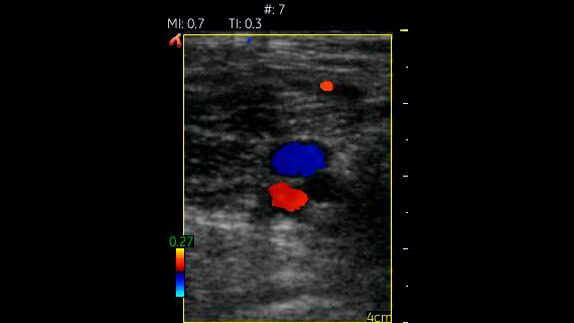

Vascular